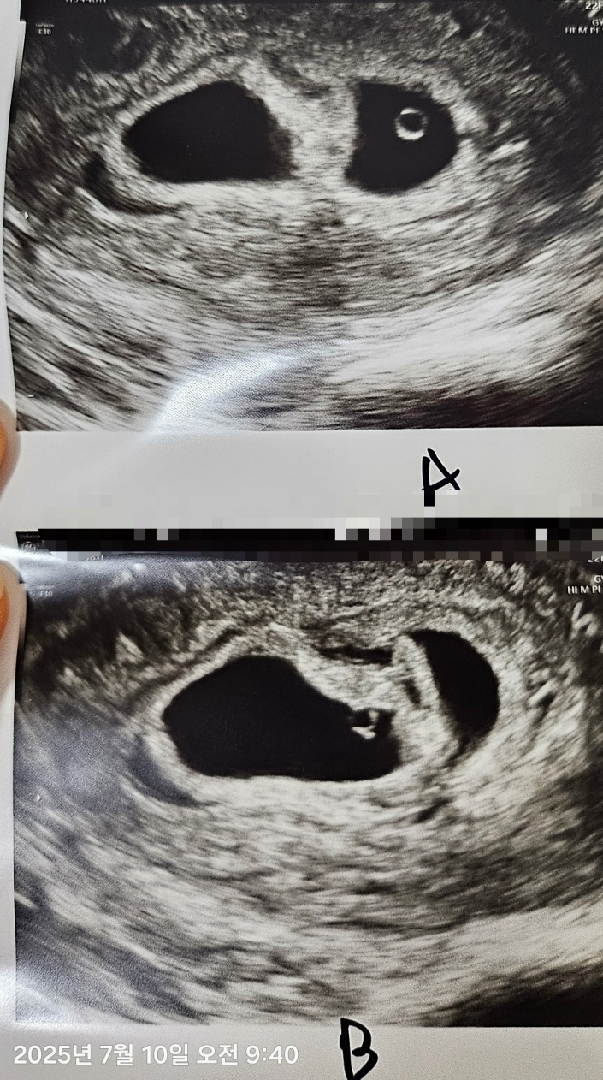

첫 초음파 ! 둥이엄마 됐어요~

아침부터 입덧지옥에 가슴을 토닥토닥 쓸어내리면서 울렁울렁이 극에 달했는데 초음파 시작하자마자 딱 보이는데 입덧은 무슨, 아무생각 없이 눈물이 왈콱 ! 또르르 흐르는데 첨느껴보는 감정이에요 노산인데 쌍둥이라는 말에 설렘 반, 걱정 반이지만 하늘이 주신 귀한 선물이네요~ 입덧주사 맞고 하루 자고 일어나니 확실히 어제 푹 잤어요~ 10일 초음파 봤고 22일 마지막 방문 난임센터 졸업이라는데, 넘 빠른게 아닌가 싶어요~ 다른 분들은 언제 졸업하시는지 궁금해요! 졸업하고도 프롤루텍스 같은 주사 계속 맞으시는지 궁금해요~~